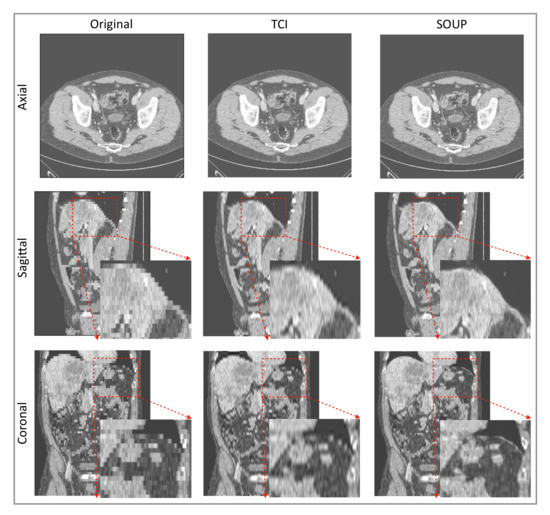

3.4. Generalization to Other Medical Imaging Modalities, e.g., CT

We also apply our scale-attention SR model to CT data. Figure 6 and Figure 7 show the SR-interpolated (SOUP) and conventionally interpolated images on abdominal and pelvic CTs. It is clear from both examples that the SR-interpolated results achieve significantly higher quality than the conventionally interpolated ones in regard to the edges, textual details, and blurring. Those comparisons demonstrate that our scale-attention SR model (SOUP) is a widely generalizable tool for different sampling factors and various applied imaging modalities, which paves the way for more advanced medical image interpolation through deep-learning SR.

Figure 6.

Example of SR interpolation on CT with a sampling factor equal to 4.8. Edges and textual details are better resolved by SR. Blurring is reduced. TCI: tricubic interpolation.

Figure 7.

Another example of SR interpolation on CT data with a sampling factor equal to 5.72. TCI: tricubic interpolation.

It was encouraging to see that our model, which was trained on MRI T1 brain data, generalized to other contrast types of MRI and CT data, and other body parts. Rather than training a different specialized model for each medical modality and body part, it is more convenient to design one model that works for all medical images to achieve SR interpolation. CT data expressed in Hounsfield units obtained from a linear transformation of the measured attenuation coefficients have different distributions from MRI data. We note here that data standardization by scaling them into a uniform range, e.g., (0, 10,000), was necessary to make the SR model compatible for different imaging modalities. Although less accurate than training a model directly on CT data, Figure 6 and Figure 7 show good performance using our T1-trained model for CT data inference. Since they are realistic applications of SR interpolation performed on poor quality data (generating thin slices from thick slices), no ground-truth data is available to calculate metrics of generated images.